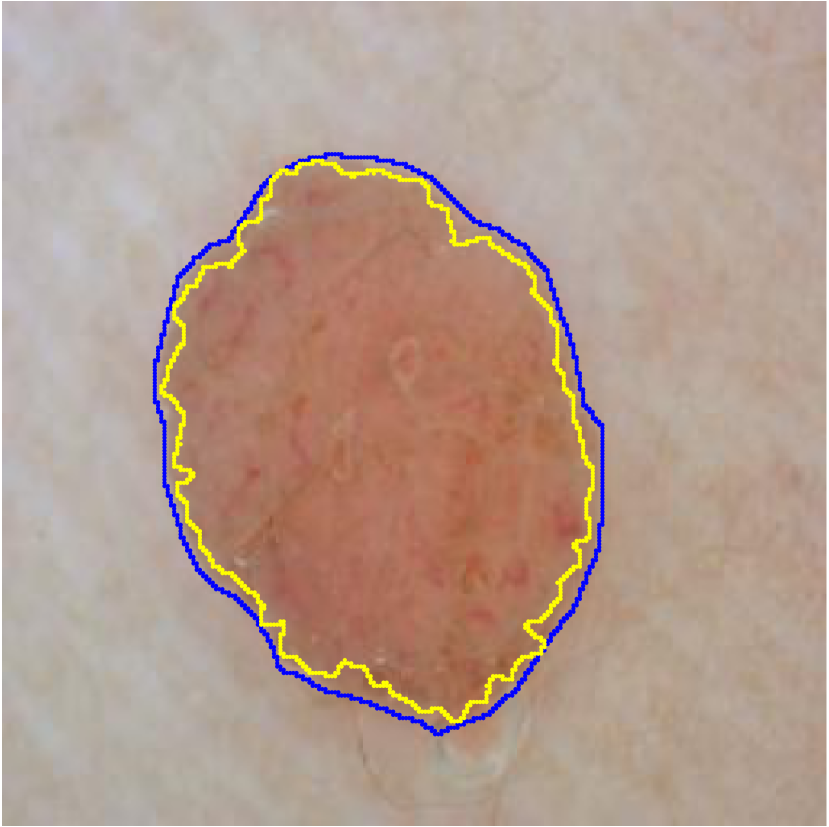

A few existing segmentation label noise approaches (Zhu et al., 2019; Zhang et al., 2020b; a) directly apply methods in classification label noise. However, these methods assume the label noise for each pixel is i.i.d. (independent and identically distributed). This assumption is not realistic in the segmentation context, where annotation is often done by brushes, and error is usually introduced near the boundary of objects. Regions further away from the boundary are less likely to be mislabeled (see Fig. 1(c) for an illustration). Therefore, in segmentation tasks, label noise of pixels has to be spatially correlated. An i.i.d. label noise will result in unrealistic annotations as in Fig. 1(b).

For each of these three datasets, we use three noise settings, denoted by , and . and are two settings synthesized by our Markov process with (expansion) and (shrinkage), respectively. Figure 4 shows examples of our synthesized label noise. We also include the mix of random dilation and erosion noise used by previous work (Zhu et al., 2019; Zhang et al., 2020b; a). This is achieved by randomly dilate or erode a mask with a number of pixels. Note that our Markov label noise can theoretically include this type of noise by setting . Detailed parameters for these settings are provided in the Appendix.

Real-world label noise. To evaluate with real-world label noise is challenging. We are not aware of any public medical image segmentation dataset that has both true labels and noisy labels from human annotators. Therefore, we use a multi-annotator dataset, LIDC-IDRI dataset (Armato III et al., 2015; Armato et al., 2011; Clark et al., 2013), and the coarse segmentation in a vision dataset, Cityscapes (Cordts et al., 2016). The LIDC-IDRI dataset consists of 1018 3D thorax CT scans where four radiologists have annotated multiple lung nodules in each scan. The dataset was annotated by 12 radiologists, and it is not possible to match an annotation to an expert. We use the majority voting as the true labels and the union of four annotations as noisy labels. We process and split the data exactly the same way as Kohl et al. (2018). Cityscapes dataset contains 5000 finely annotated images along with a coarse segmentation by human annotators that we use as the “noisy label”. We only focus on the ‘car’ class because (1) cars are popular objects and are frequently included in images; (2) the coarse annotation of cars is very similar to noisy annotation in medical imaging – they are reasonable distortions of the clean label without changing the topology. See Figure 4(c) for an example. The detailed settings of LIDC-IDRI and Cityscapes can be found in Appendix A.2.1.

Table 1 shows the segmentation results of different methods with synthetic noisy label settings on JSRT , ISIC 2017 and Brats 2020 dataset. Note that QAM cannot be applied to Brats 2020 dataset because their network is designed for 2D only. We compare DICE score (DSC) on testing sets (against the clean labels). For each setting, we train 5 different models, and report the mean DSC and standard deviation. In and , where biases show up in noisy labels, the proposed method outperforms the baselines by a big leap in total case. The compared methods, however, only work when little bias is included, like . is equivalent to setting in our Markov model, resulting in . We also test the proposed method on real-world label noise, results shows in Table 2. Figure 5 shows examples of label correction results. We provide more qualitative results in the Appendix A.4.